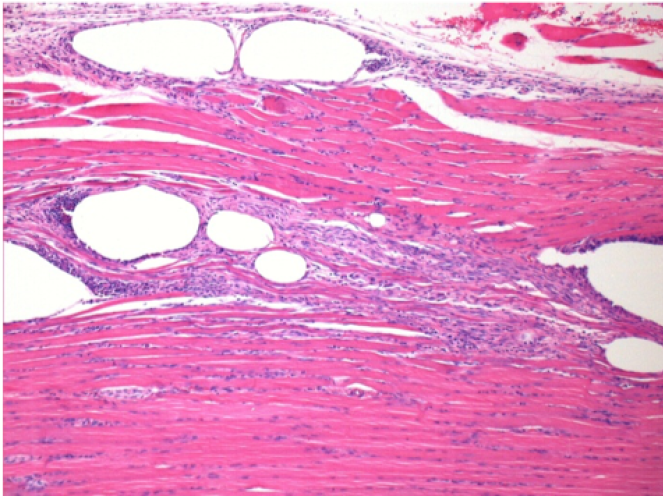

10 días después de la inyección de Endopeel

10 días después de la inyección de Endopeel 0,1 ml en el músculo pretibial derecho.

Aquí puede ver la formación de las vacuolas que están rodeadas de linfocitos. Las vacuolas son diferentes a la necrosis tisular. La presencia de linfocitos está relacionada con la permeabilidad de las membranas celulares.

L : Control-100xD10

R:100xD10

R :200xD10

R :400xD10